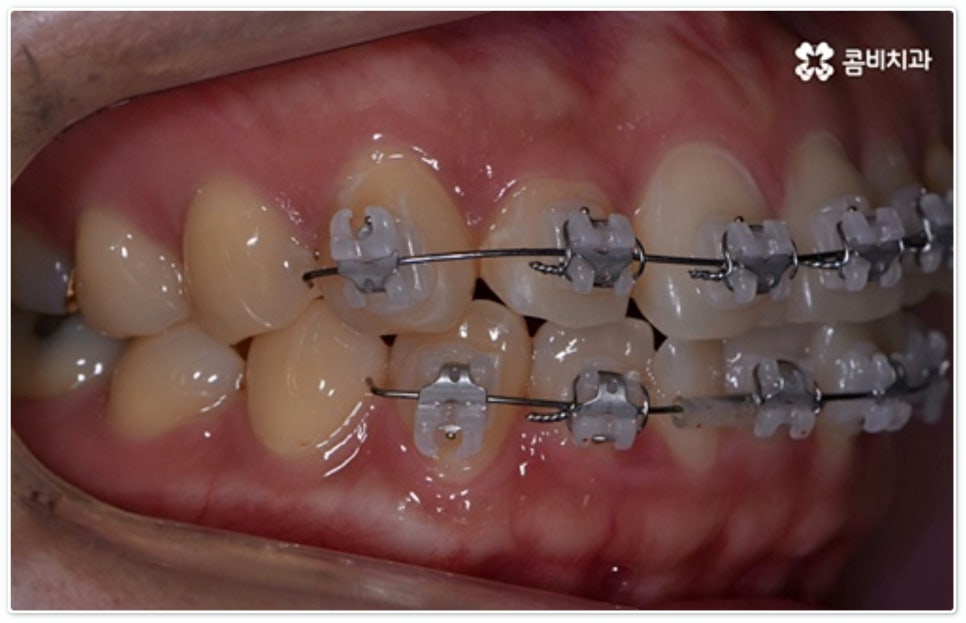

그렇지 않고 전후방 각도 조절 또는 단순 횡적인 움직임으로 치열 개선이 가능한 케이스는 부분 교정을 진행하는데, 사진에서 보시는 사례가 바로 그런 경우에 속하고 있습니다. 앞니 6개에만 브라켓을 부착하였는데 보시다시피 치아 색상과 유사한 세라믹 재질의 장치를 이용하여 심미성 또한 높여 주었음을 알 수 있어요.

토끼 앞니, 나비 앞니 중 이와 같이 어금니 교합은 정상이지만 앞니 또는 일부 치아가 돌출되거나 방향이 틀어진 경우 뿐 아니라 다른 치료 (보철 치료나 임플란트 시술) 를 위해 먼저 부분적으로 치아 이동이 필요한 경우, 교정 치료를 받은 적이 있으나 앞니 또는 주변 치아 배열이 다시 틀어진 경우 등에 있어서도 부분 교정이 이용될 수 있습니다. 그러므로 ‘치료가 오래 걸릴 것이다’, ‘장치가 보이는 게 많이 부담스럽다’, ‘재교정을 받는 것이 무섭다’ 등등 여러 걱정으로 교정 치료 시기를 미루시지 말고 필요한 경우 상담부터 차근차근 진행해 보시면 좋을 거예요.